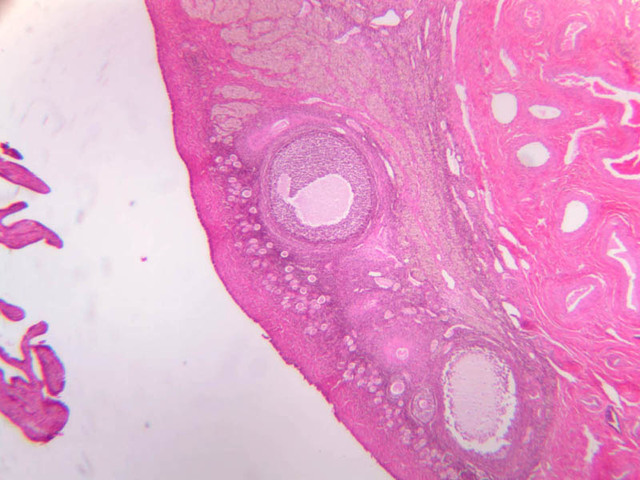

The ovary is a somewhat oval and slightly flattened organ situated near the fimbriated end of the uterine tube (B-94, monkey ovary, H&E [1x, 1x]; B-95, monkey ovary, H&E [1x-labeled, 1x]; B-96, monkey ovary and tube, H&E [1x]; B-54, H&E [1x, 1x]). Its exposed surface is covered by a mesothelial sheet of squamous or cuboidal epithelium. Just deep to this is an ill defined area of dense fibrous connective tissue referred to as the tunica albuginea (B-96 [2.5x-labeled, 10x-labeled, 20x, 40x]).

The ovary has two major regions – the cortex and the medulla. The cortex is the broad peripheral area containing follicles in various stages of development, whereas the medulla is the more central area displaying profiles of large blood vessels. These blood vessels gain entrance via the mesovarium. The division between the cortex and medulla is indistinct. In the cortex, stromal cells occupy the areas between the follicles. These cells are closely packed, fusiform (spindle shaped), and have the potential to differentiate into a specialized component of the maturing follicle (theca folliculi).

Primordial Follicle

Primordial follicles are located in periphery of cortex. They contain a large round oocyte surrounded by a single layer of flattened follicular cells. The follicles occupying this category are inactive. They are the population from which follicular growth begins. Primordial Follicles [Inactive] (slide B-94 [2.5x, 10x, 20x, 40x] [10x, 20x, 40x-labeled] [10x, 20x, 40x]; B-96 [2.5x, 10x, 20x, 40x, 40x, 40x, 40x]).